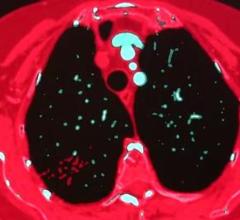

CT Angiography (CTA)

This channel includes news and new technology innovations for CT systems using a series of X-ray images to create an image volume data set that can be sliced or manipulated on any plane using advanced visualization software. The section includes computed tomography scanners, CT contrast agents, CT angiography (CTA and CCTA), CT perfusion, spectral CT (dual souce CT), and interative reconstruction dose reduction software.